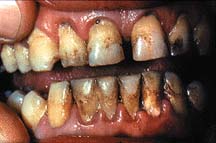

Parodontite severe

mobilitate dentara accentuata pâna la avulsia dintilor

migrari patologice

halena constanta

hiperestezie dentinara datorata denudarii radacinii

pungi parodontale > de 6 mm

resorbtie osoasa accentuata